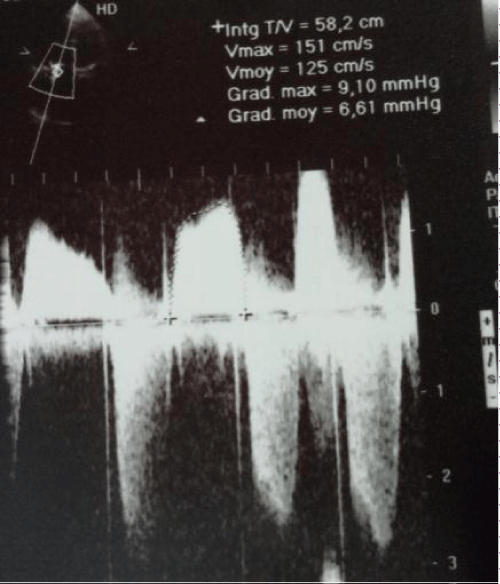

A 62 year old woman presented with right sided heart failure symptoms encluding dyspnea, lower exteremity edema fatigue and ascites. She had a history of mitral stenosis since the age of 10. She had originally under gone mitral and aortic valve replacement at the age of 40, along with a tricuspid valve annuloplasty with a carpentier Edwards tricuspid ring for severe tricuspid regurgitation (TR). Ten year later she under went a tricuspid valve replacement with a bioprothesis due to persistant of severe tricuspid regurgitation. She remained a symptomatic until the age of 61, her fatigue increased and lower extreme tyedema worsened when she was admitted to hospital. The physical examination revealed signs of right heart failure of right heart failure. The patient was on atrial fibrillation. The echo cardiogram revealed severe thickened leaf lets of the bioprothetic tricuspid valve, with a severe tricuspid stenosis and mild regurgitation. The mean diastolic gradient across the tricuspid valve was 12 mmHg (Figure 2).

According to hemodynamique measurements, once inflation was complete, the mean pressure gradient was reduced to 5 mmHg. The right atrial pressure dropped from 46 mmHg to 23mmHg. Post procedure transthoracic echo cardiography showed that mean gradient was reduced from 12 mmHg to 6 mmHg (Figure 3). The tricuspid régurgitation was inchanged. The patient tolerated the procedure well.